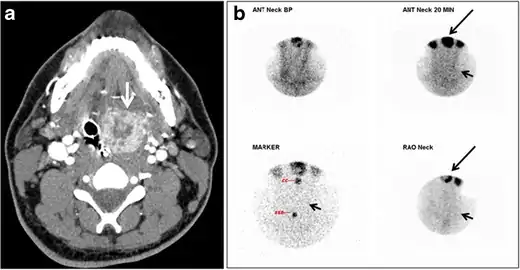

Fig. 8. A 48-year-old male patient post total thyroidectomy with PTC recurrence. a Transverse greyscale ultrasound of the neck demonstrates a left thyroid bed heterogeneous, predominantly hypoechoic irregular lesion with calcifications (white arrow). b A spot image of iodine 123 total body scan of the neck demonstrate a focus of abnormal radiotracer uptake at the left thyroid bed (Black arrows) between the annotated markers. c Enhanced axial CT scan of the neck demonstrates an enhancing large left thyroid bed mass (white arrow) with no calcifications. The lesion exerts a mass effect on the oesophagus (black arrow) and is inseparable from the trachea.[1]